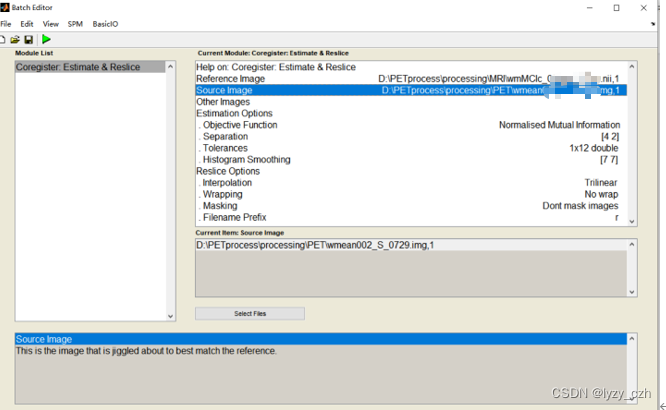

4)将wmeanxxxx.hdr配准到自己的MRI图像wmxxxx.nii上,打开Coregister(Est & Res),只修改Reference Image和Source Image;

注意:如果只需要处理PET图像,MRI可以使用模板来进行配准和去头骨影像(这里是配准到同一患者的SMRI预处理后的图像 wmxxxx.nii是SMRI预处理后的图像)

生成如下文件:

此时的PET与MRI大小相同